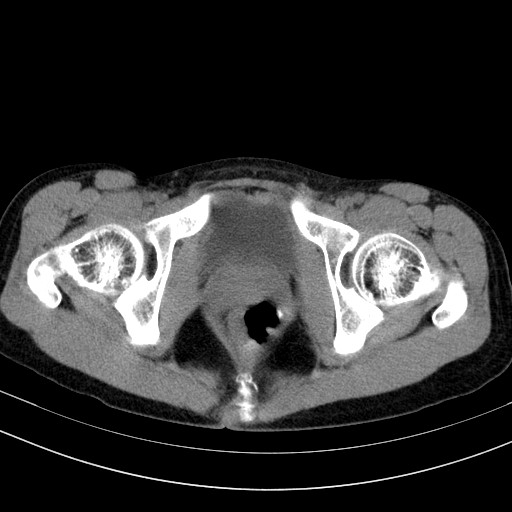

以下是引用卜一在2009-4-7 5:08:00的发言:[br]宫颈癌可能。支持!

以下是引用随光逐影在2009-4-7 8:17:00的发言:[br]考虑宫颈占位性病变(宫颈癌?);建议行进一步检查。

以下是引用jiangjing在2009-4-7 16:46:00的发言:[br]宫颈增大,结构不清,右侧附件区可疑囊样占位,建议增强及mri 检查